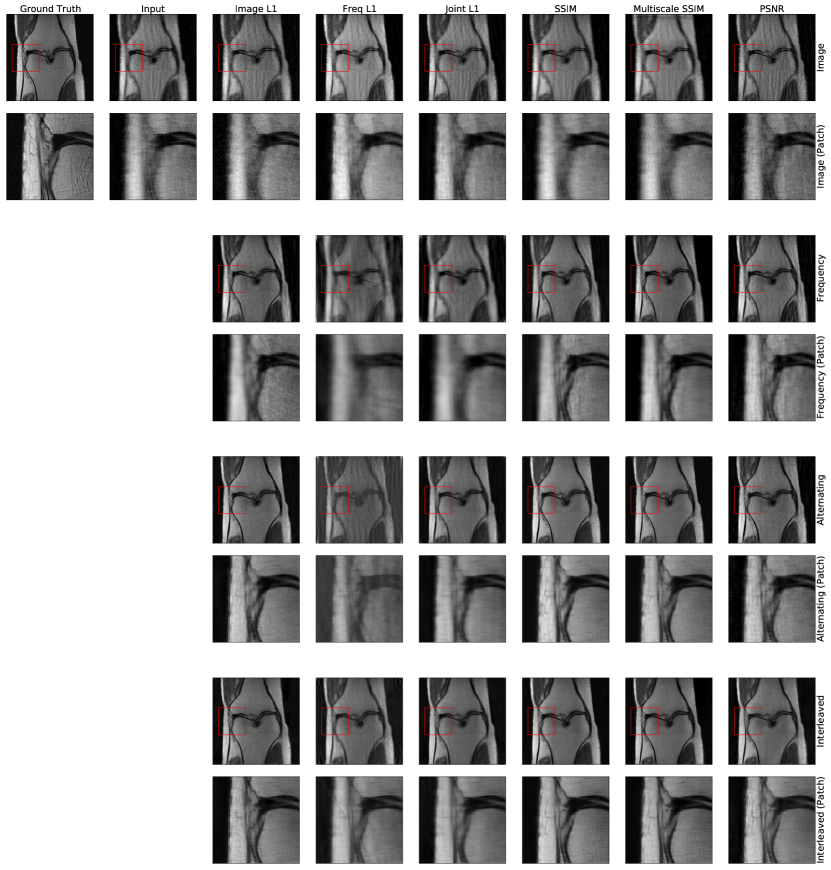

We compare the Interleaved and Alternating networks with Frequency and Image baseline methods, as well as the top three methods submitted to the single coil track of the FastMRI challenge at https://fastmri.org.

A.2 Training Loss and Evaluation Metrics

We evaluate and compare the networks trained with a variety of loss functions and assess reconstruction quality via different quality metrics. We train Frequency, Image, Interleaved and Alternating networks with seven loss functions: image space L1 error, frequency space L1 error, a joint L1 metric summing image and frequency L1 errors, SSIM (Wang et al., 2004), multiscale SSIM (Wang et al., 2003), and PSNR (Huynh-Thu and Ghanbari, 2008). The joint L1 metric weighs the frequency space L1 error by 0.1 relative to the image space L1 error to account for differences in the error magnitudes. The SSIM and multiscale SSIM scores are computed with window size and constants , .

A.3 Results

Our results on the knee undersampled reconstruction task replicate the trends observed in the brain undersampled reconstruction task. Joint networks outperform single-domain networks, as reported in Table 2. This suggests that our joint layers can successfully process acquired, complex-valued MRI data. Further, Table 2 confirms that the success of joint learning is not specific to a certain loss landscape. Qualitative examples of reconstructions from networks trained with various loss functions are shown in Fig. 11.

The reconstructed images produced by the larger Interleaved network are qualitatively similar to those produced by the top three methods on the FastMRI leaderboard (Fig. 12). Table 3 reports reconstruction quality measures for Interleaved network and the top single-slice methods on the FastMRI benchmark. Interleaved network achieves results that are close to the state of the art architectures specifically tuned for this task. We emphasize that our goal is not to attain state of the art performance on the FastMRI benchmark, but rather to show that simple layers comprised of both frequency and image space convolutions achieve reasonable performance on this benchmark while offering flexibility for correcting a wide range of other artifacts, and for correcting multiple artifacts present simultaneously.